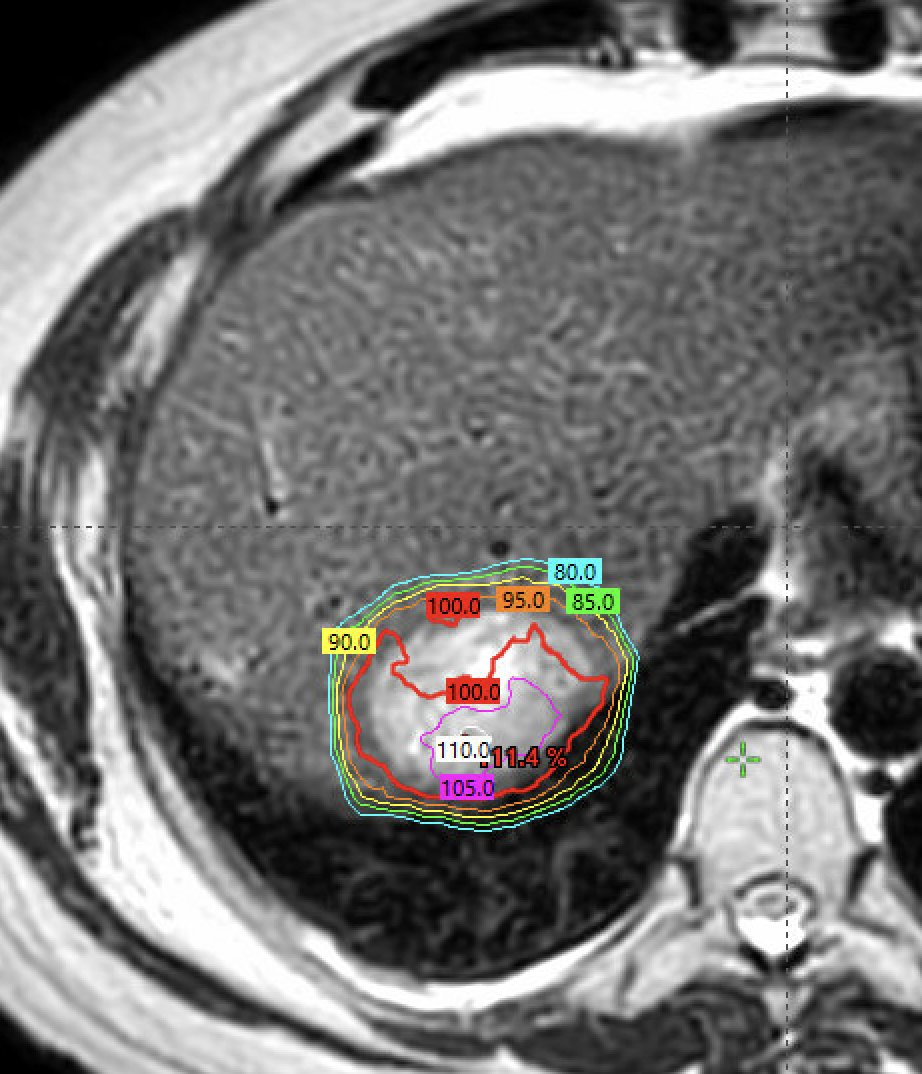

Always wait >4 weeks. Also check CEA first. If positive CEA, no ctDNA needed. CEA is 60 dollars. ctDNA>1000 dollars.

Dr. Nina Niu Sanford

Sharing an instructive case. Treated isolated liver met single fx SBRT (40Gy). ctDNA 5 days later increased 80 to 1100!! PET 2 wks after negative (tumor gone), & ctDNA 3 wks later <10. Lesson - if checking ctDNA, wait (at least a few wks?) after SBRT. Have others seen this?